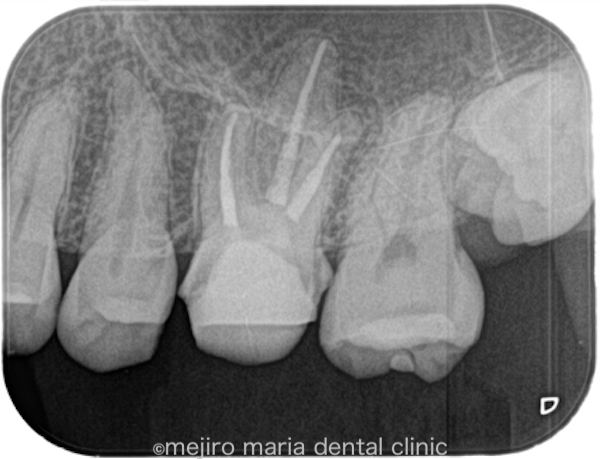

左上6番(上顎左側第2大臼歯)は既に根管治療が施されており、根尖性歯周炎は根尖に確認されないものの、以前の治療の質は良い状態ではない(質が低い)ことが予想できます。根管治療の質を高める意味合いで再根管治療をご提案させていただきました。